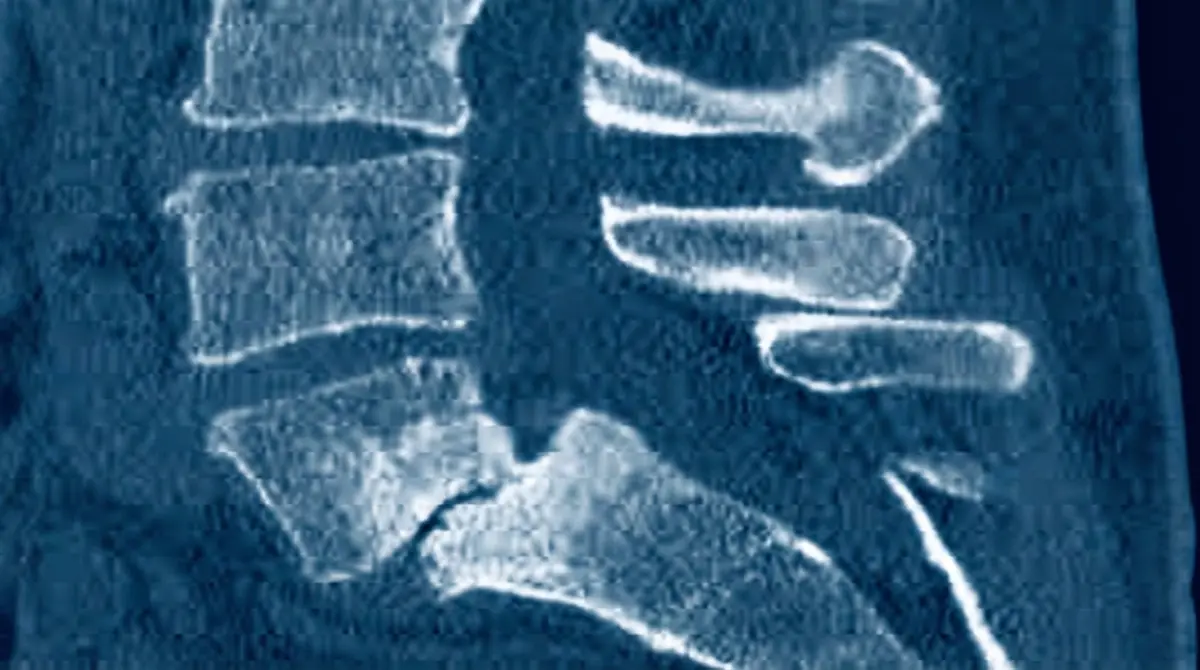

📉 Espondilolistese Ístmica L5–S1

> "É como se, após a fratura do ístmo (espondilólise), a vértebra L5 perdesse a âncora traseira e 'escorregasse' para frente sobre o sacro. É o desfecho da espondilólise não tratada — a vértebra desliza gradualmente."

Deslizamento anterior de L5 sobre S1 (sacro) devido a uma fratura prévia no ístmo (espondilólise). Sem a conexão posterior intacta, a vértebra inclina para frente. É mais comum em adolescentes e jovens adultos, especialmente atletas com história de espondilólise.